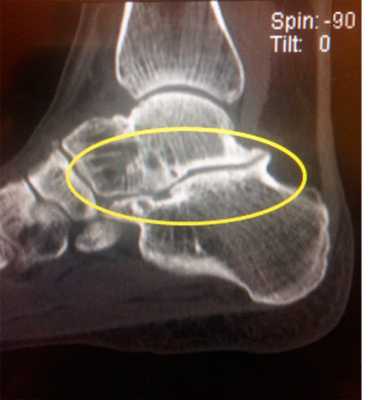

Пациент М. 1980 г.р., травму получил при падении на стопы с высоты 1,5 метра. Лечился по месту жительства (в травмпункте районной больницы) консервативно в гипсовой повязке в течение 14 дней. Консультирован в травматологическом отделении ФГБУ «УНИИТО им. В.Д. Чаклина» Минздрава РФ, предложено оперативное лечение. При поступлении кожные покровы стопы чистые, без признаков воспаления и сдавления тканей. Стопа отечна, уплощена. На рис. 1 представлены рентгенограммы пациента. Прооперирован через 2 недели после травмы. Операция состоит из двух этапов. Первый этап заключается в наложении дистракционного аппарата. Проводятся две спицы 1,8 мм во фронтальной плоскости: первая через нижнюю треть диафиза большеберцовой кости, вторая через бугор пяточной кости (рис. 2). Спицы фиксируются в дистракционном аппарате, выполненном из двух полуколец, соединенных между собой двумя телескопическими тягами. Особое расположение полуколец, фиксация спиц на концах полуколец, крепление кронштейнов для телескопических тяг обеспечивает тракцию пяточной кости в необходимом направлении с использованием минимального количества спиц и внешних опор при сохранении необходимого поля обзора для проведения рентгенологического и визуального контроля репозиции и фиксации. Второй этап - закрытая элевация импрессированной суставной поверхности и окончательная репозиция пяточной кости. Через разрез длиной до 1 см по латеральному краю ахиллова сухожилия (рис. 3) в месте его прикрепления к пяточной кости под соответствующий фрагмент подводится элеватор (рис. 4), манипуляцией которым устраняется смещение и выполняется провизорная фиксация спицами 1,5 мм (рис. 5). При сагиттальном раскалывании суставной фасетки целесообразно проведение одного-двух винтов субхондрально (рис. 6). Стержень вводится с дорзальной поверхности пяточной кости по ее оси через разрез до 2 см по предварительно сформированному остеотомом каналу (рис. 7, 8). Далее через проколы кожи с помощью кондуктора (рис. 9) выполняется запирание винтами с латеральной поверхности, внешнее устройство демонтируется. Достигнуто удовлетворительное стояние отломков (рис. 10).

Рис. 3. Под контролем ЭОП из разреза длиной до 1 см латеральнее места прикрепления ахиллова сухожилия выполняется элевация суставной поверхности пяточной кости

Рис. 4. Устранение смещения отломка

Рис. 5. Провизорная фиксация репонированной суставной поверхности спицами

Рис. 6. Окончательная фиксация компрессирующим винтом, введенным субхондрально